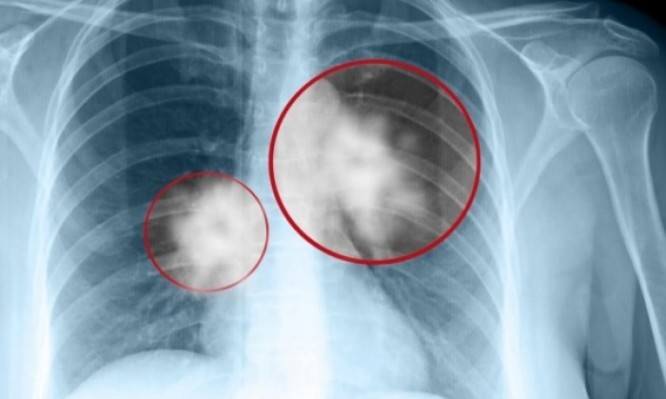

-«Όλα ξεκίνησαν στη διάρκεια ενός ταξιδιού μου στην Ελλάδα και λόγω των διαδηλώσεων στο κέντρο της Αθήνας, έμεινα σ’ ένα μικρό ξενοδοχείο στην Κηφισιά. Ένα πρωινό περπάτησα στην περιοχή, γύρω από το ξενοδοχείο, κι έτυχε να περάσω μπροστά από ένα σχολείο οπότε είδα δύο μαυροντυμένες γυναίκες να δίνουν δωρεάν τσιγάρα σε μικρά κορίτσια. Τις πλησίασα διότι ήθελα να δω τι έκαναν, δεν μιλούσαν ούτε ελληνικά, ούτε αγγλικά, αλλά μοίραζαν τσιγάρα σε κοριτσάκια 11 και 12 χρονών. Τηλεφώνησα στον εξάδελφό μου, τον Παναγιώτη Μπεχράκη, ο οποίος είναι γιατρός πνευμονολόγος και καθηγητής στο Πανεπιστήμιο και τον ρώτησα τι γίνεται εδώ; Επιτρέπει η κυβέρνηση σε αλλοδαπούς να μοιράζουν τσιγάρα σε μικρά κορίτσια και αγόρια; Θα αντιμετωπίσετε μεγάλη καταστροφή στα επόμενα τριάντα χρόνια. Εσύ που είσαι γιατρός γνωρίζεις ότι το 80% του καρκίνου των πνευμόνων προέρχεται από το κάπνισμα των τσιγάρων. Αυτά τα παιδιά θα καπνίζουν κατά τα επόμενα τριάντα χρόνια και θα προκύψει πολύ σοβαρό πρόβλημα. Θα πρέπει να κάνουμε κάτι» Η Ελλάδα ήταν η νούμερο ένα χώρα στην Ευρώπη, δαπανώντας δισεκατομμύρια στην αγορά καπνού. Η εκστρατεία κατά του καπνίσματος είχε ως αποτέλεσμα η Ελλάδα να πέσει από την πρώτη, στην τρίτη θέση του ευρωπαϊκού χάρτη καπνίσματος. Βεβαίως, και η αύξηση της φορολογίας στα τσιγάρα έχει βοηθήσει πολύ. Πάνω από όλα όμως είμαι πολύ εντυπωσιασμένος μ’ αυτά τα παιδιά, τα Ελληνόπουλα. Είναι πολύ επιδεκτικά μαθήσεως και έχουν γνώσεις».

-Στις γυναίκες θα έδειχνα στατιστικές εγκυμοσύνης. Στους άντρες θα εξηγούσα πόσο επιζήμιο είναι το κάπνισμα. Το σώμα δεν μπορεί να απορροφήσει μη φυσικά προϊόντα, ούτε να μεταβολίσει τις πρόσθετες ουσίες ενός τσιγάρου. Ο καλύτερος τρόπος για να πειστεί κάποιος να κόψει το κάπνισμα, είναι η εκπαίδευση, δείχνοντας τη θανάσιμη δύναμη του καπνού.